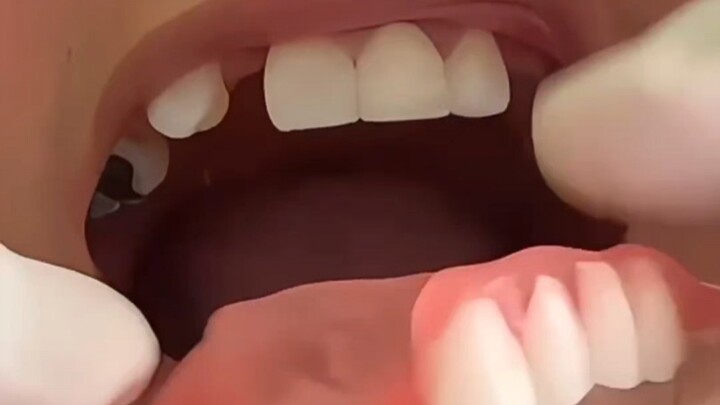

لم أفرش أسناني منذ 10 سنوات، سأزيل كل ذلك دفعة واحدة!

إذا كانت أسنانك على هذا الشكل، فلا تلجأ بسهولة إلى تركيب التيجان، فالإصلاح في مكانه الأصلي أكثر جمال